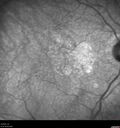

99 year old man with retinal angiomatous proliferation (type III CNVM) in the left eye. VA was 20/32